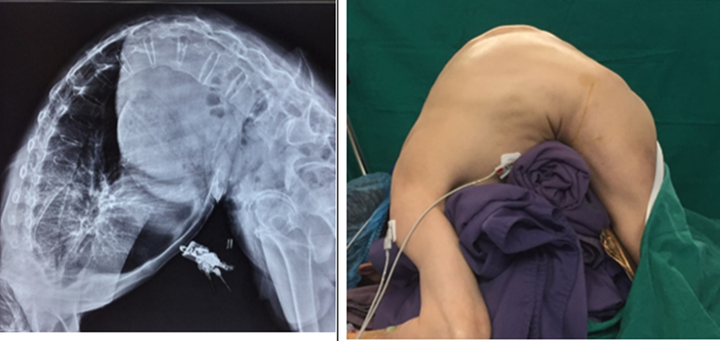

Hình ảnh lưng bệnh nhân trước khi phẫu thuật.

Theo các bác sĩ, anh nhập viện trong tình trạng bị gù rất nặng toàn bộ cột sống, đỉnh đầu còn thấp hơn cả vùng đỉnh gù cột sống, tầm nhìn chỉ 1-2 mét, không khó thở, mệt khi đi lại nhiều (200-300m), bụng gấp hết mức, có rất nhiều nếp gấp lằn bụng, mặt cúi gần sát đất, các khớp vai, khớp háng, khớp gối vận động bình thường.

Sau khi làm các xét nghiệm cận lâm sàng, bệnh nhân được chẩn đoán gù toàn bộ cột sống do viêm cột sống dính khớp. Bệnh nhân được chỉ định phẫu thuật nắn chỉnh biến dạng gù cột sống.